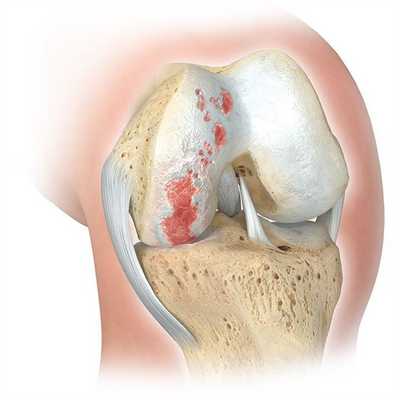

Главным показанием к оперативному вмешательству является гонартроз. Это дегенеративное заболевание коленного сустава, проявляющееся постепенным разрушением хрящевой ткани и деформацией нижней конечности. На поздних стадиях гонартроза у пациентов формируются вальгусные и варусные деформации. Объем движений ограничивается, возникает хронический болевой синдром.

Вмешательство рекомендуется проводить при удовлетворительном состоянии хрящевой поверхности костей и изолированном поражении одного участка коленного сустава. Такой метод коррекции дает возможность сохранить подвижность нижней конечности у молодых пациентов.

Эффективность лечения зависит от возраста, пола и массы тела пациента. Неудовлетворительные результаты операции могут быть обусловлены пожилым возрастом больного, значительным поражением костей и разрушением гиалинового хряща.